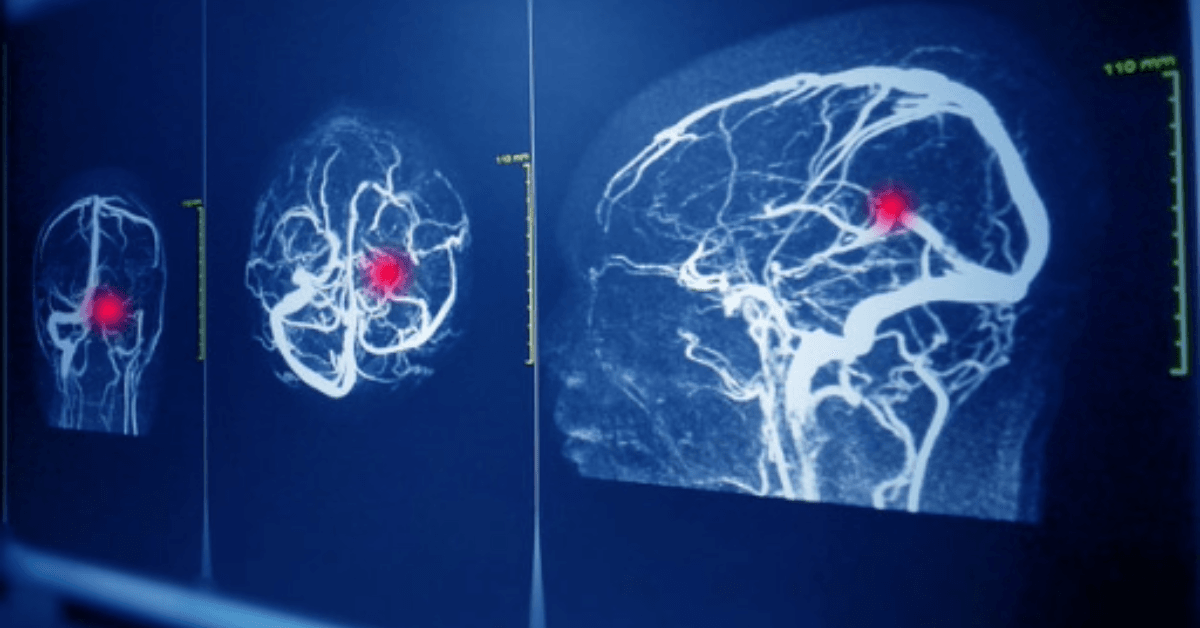

Introdução A angiografia é um procedimento médico amplamente utilizado para visualizar vasos sanguíneos e diagnosticar condições vasculares. Entretanto, pacientes que fazem uso de anticoagulantes, como a varfarina, precisam de cuidados especiais antes de se submeterem a esse exame. A combinação…